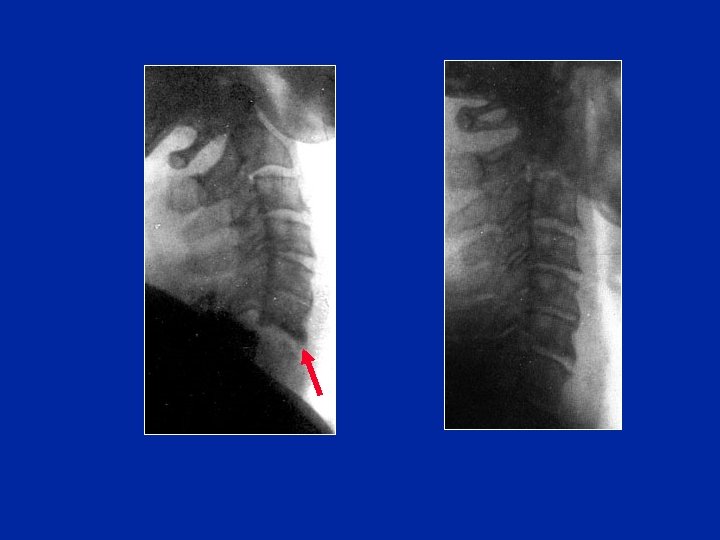

Instabilité Fracture associée de l’arc post. Subluxation

Entorse “bégnigne” Après collier 1 mois Radio en flexion

L’instabilité justifie une arthrodèse Arthrodèse intersomatique antérieure